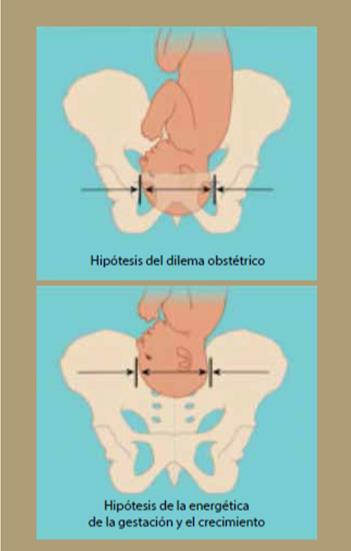

Varias evidencias del dilema obstétrico indican que al nacimiento puede haber un conflicto entre la salida de una cabeza grande y el estrecho diámetro del canal pélvico, que se resolvió haciendo que el feto salga a una edad en la que todavía es inmaduro. Sin embargo, algunas inconsistencias entre esos datos han llevado a la proposición de otra hipótesis que parece explicar igualmente bien la necesidad del nacimiento de un feto prematuro. Esta se denomina EGG (siglas en inglés de “energética de la gestación y el crecimiento”).23

Durante el nacimiento, 2 de las características típicas del género humano, un cerebro grande y la bipedalidad, parecen estar una contra la otra. El cerebro grande y la cabeza grande que lo contiene son difíciles de empujar a través del canal pélvico, lo que requeriría una pelvis más ancha, aunque eso comprometería el bipedalismo. Se ha dicho que la manera como la evolución solucionó ese problema, que se conoce como el dilema obstétrico, fue acortando la duración del embarazo, de manera que los fetos nacen antes de que la cabeza sea demasiado grande y, como resultado, comparados con otros primates los bebés humanos son inmaduros en términos de su capacidad motora y cognitiva.

Todos esos resultados llevaron al desarrollo de una nueva hipótesis para explicar la temporalidad del nacimiento humano, que fue llamada EGG. Esta hipótesis propone que los bebés nacen cuando la madre ya no puede poner más energía en el embarazo y el crecimiento fetal, de manera que la limitación principal en la longitud del embarazo es la energía de la madre.

Nuestros cuerpos tienen un límite en la cantidad de calorías que pueden quemar en un día, y durante el embarazo las mujeres se acercan a ese límite y dan a luz poco antes de llegar a él. Esos límites metabólicos también explican por qué los bebés humanos son tan inútiles comparados con los bebes de primates como chimpancés, que empiezan a gatear en un mes, mientras los humanos lo hacen hasta aproximadamente los siete meses. Para un humano el dar a luz a un bebé con el mismo nivel de desarrollo de un chimpancé requeriría un embarazo de 16 meses y eso colocaría a las madres más allá de sus límites energéticos. De hecho, parece que solamente un mes más de embarazo hace que las madres entren en la zona de peligro metabólico. Por supuesto, la EGG daría otra forma al dilema obstétrico, ya que no sería el tamaño ni la forma de la pelvis femenina la limitación para el nacimiento de un bebé con una cabeza capaz de contener un cerebro grande.

La figura 14 muestra un diagrama que intenta explicar las diferencias entre las 2 hipótesis que resuelven el dilema obstétrico y aquella basada en la energía de la madre se explica con detalle en la figura 15, donde se ve que la demanda de energía fetal (círculos negros, kcal/día) aumenta exponencialmente durante la gestación. El gasto en energía materna (cuadros grises) se eleva durante los primeros 2 trimestres, llegando a un tope metabólico en el tercero, conforme el requerimiento de energía total se acerca a 2.0 × tasa metabólica basal (BMR, por sus siglas en inglés, basic metabolic rate). Los requerimientos en energía fetal proyectados para un crecimiento más allá de 9 meses (línea punteada) exceden rápidamente las tasas metabólicas máximas sostenibles por las madres humanas. Después del nacimiento (flecha) las demandas energéticas del feto aumentan más lentamente y los requerimiento maternos de energía no exceden 2.1 × BMR. El gasto en energía materna requerido para un desarrollo fetal similar al del chimpancé recién nacido (infante de 7 meses, símbolos con asterisco) implicaría requerimientos en energía maternal mayores de 2.1 × BMR25-27.

Figura 14 Diagramas de las hipótesis del dilema metabólico y de la energética de la gestación y el crecimiento (EGG).